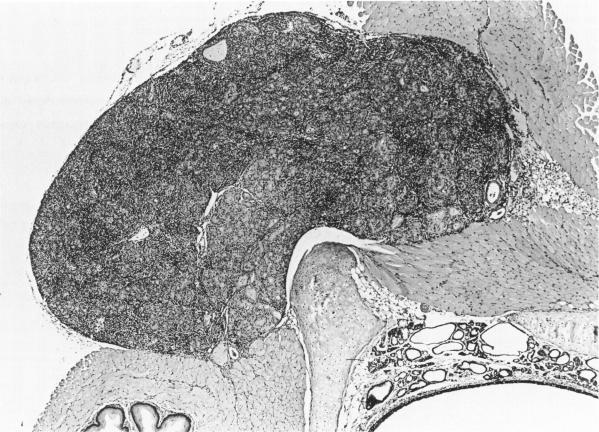

Animal model of human disease. Lymphocytic thyroiditis. Autoimmune thyroiditis in rats induced by thymectomy and irradiation.

Am J Pathol. 1982 Feb;106(2):300-2.